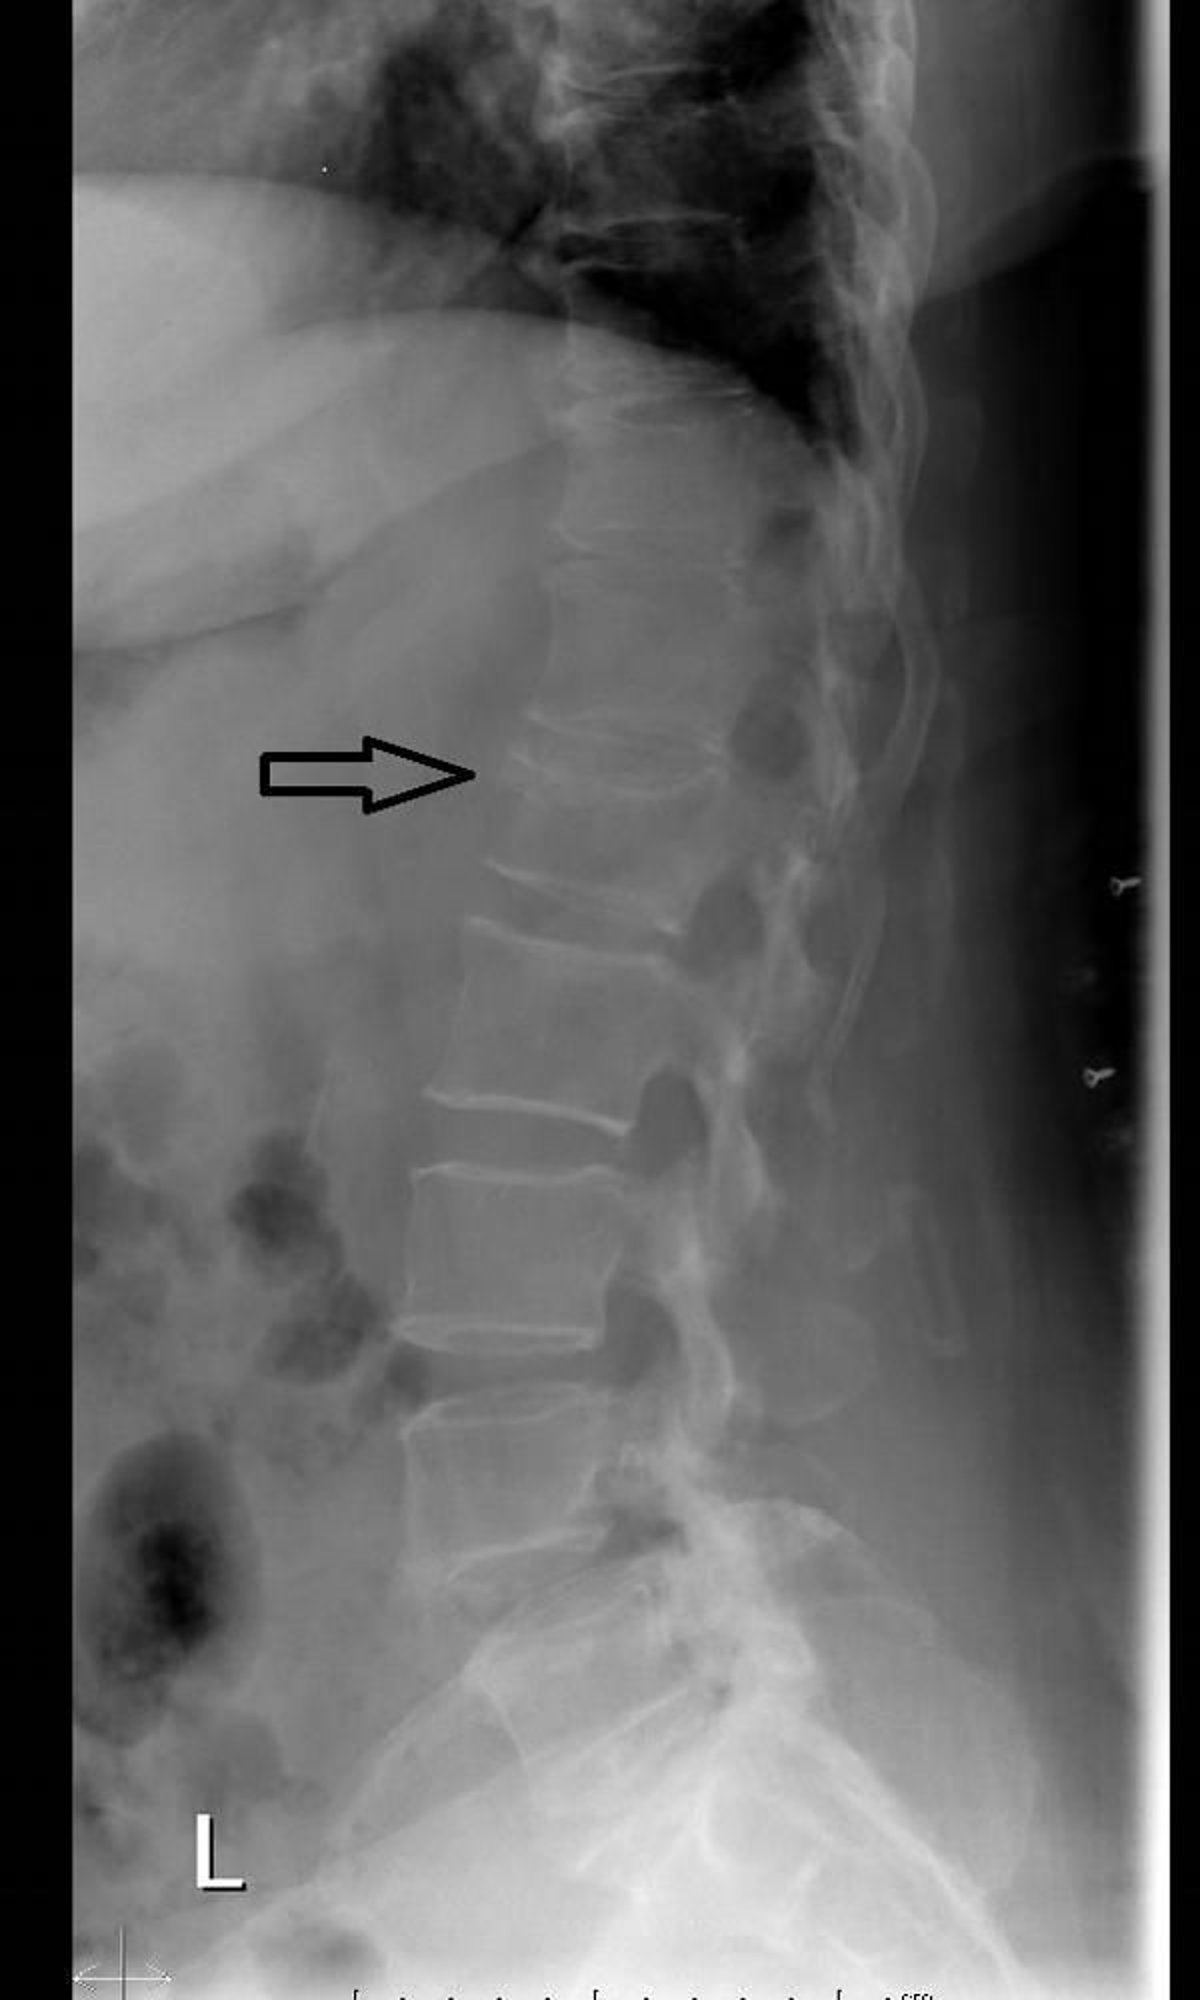

Fractura de compresión vertebral (radiografía)

Esta radiografía lateral de la columna muestra pérdida de altura y acuñamiento anterior debido a una fractura por compresión vertebral.